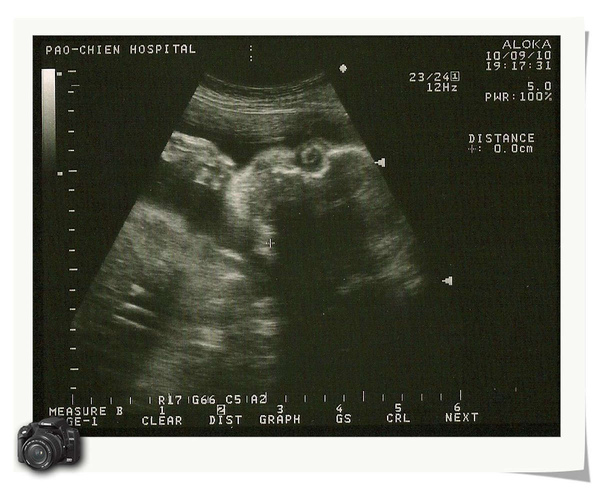

時間過得真快,小寶弟已經29週囉!昨天去產檢,已經1600G,醫生說頭圍大一週,肚圍大兩週,要我這個孕婦少喝甜的飲料,忌澱粉類食物,天啊!!夏天耶!上班又沒冷氣,又要在外面曬太陽,不能喝飲料會要我的命啊!但是為了避免到時候生不出來,我還是節制一點好,喝個三分糖或無糖好了,哈哈....

這是側睡的姿勢,眼窩很深唷!希望是個大眼睛,哈....小寶弟的大肚肚,快跟他娘我的肚子一樣大了leaf0817 發表在 痞客邦 留言(0) 人氣(31)